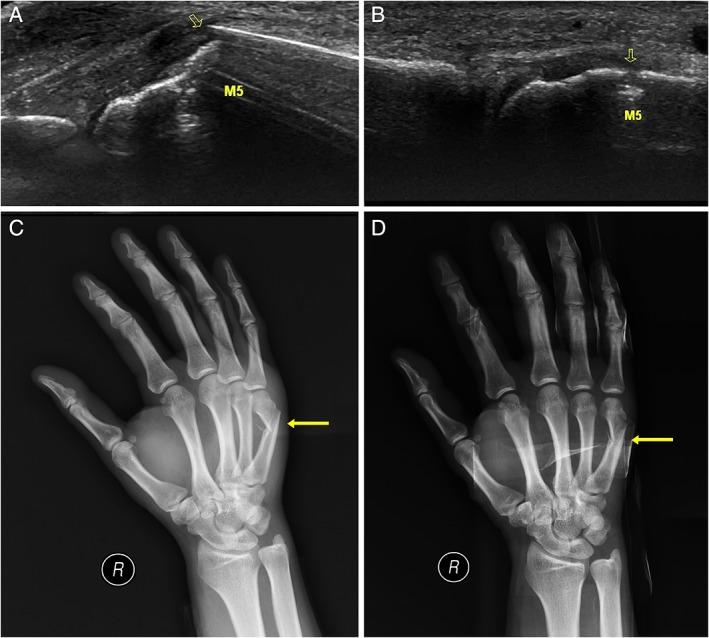

Twenty-four patients with acute metacarpal fractures were randomly divided into experimental and control groups, with 12 patients in each group. Ultrasound-guided closed reduction and fixation were performed in the experimental group, whereas C-arm fluoroscopy-assisted fixation was performed in the control group. Patients in both groups were followed to compare the treatment efficacy.

Ultrasound-guided closed reduction and minimally invasive fixation is an effective treatment of metacarpal fractures and can reduce exposure to x-ray radiation.